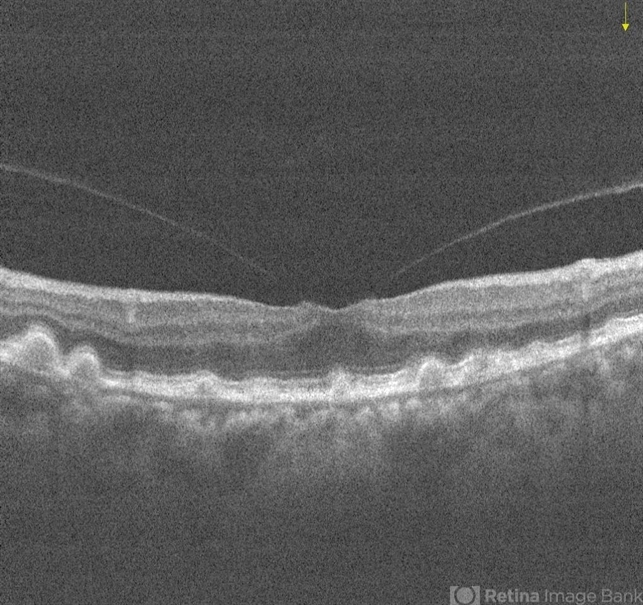

- drusenoid deposit, vitreomacular traction (VMT)

- Left eye OCT of same 73-year-old female showing drusenoid PED and Vitreomacular Adhesion .